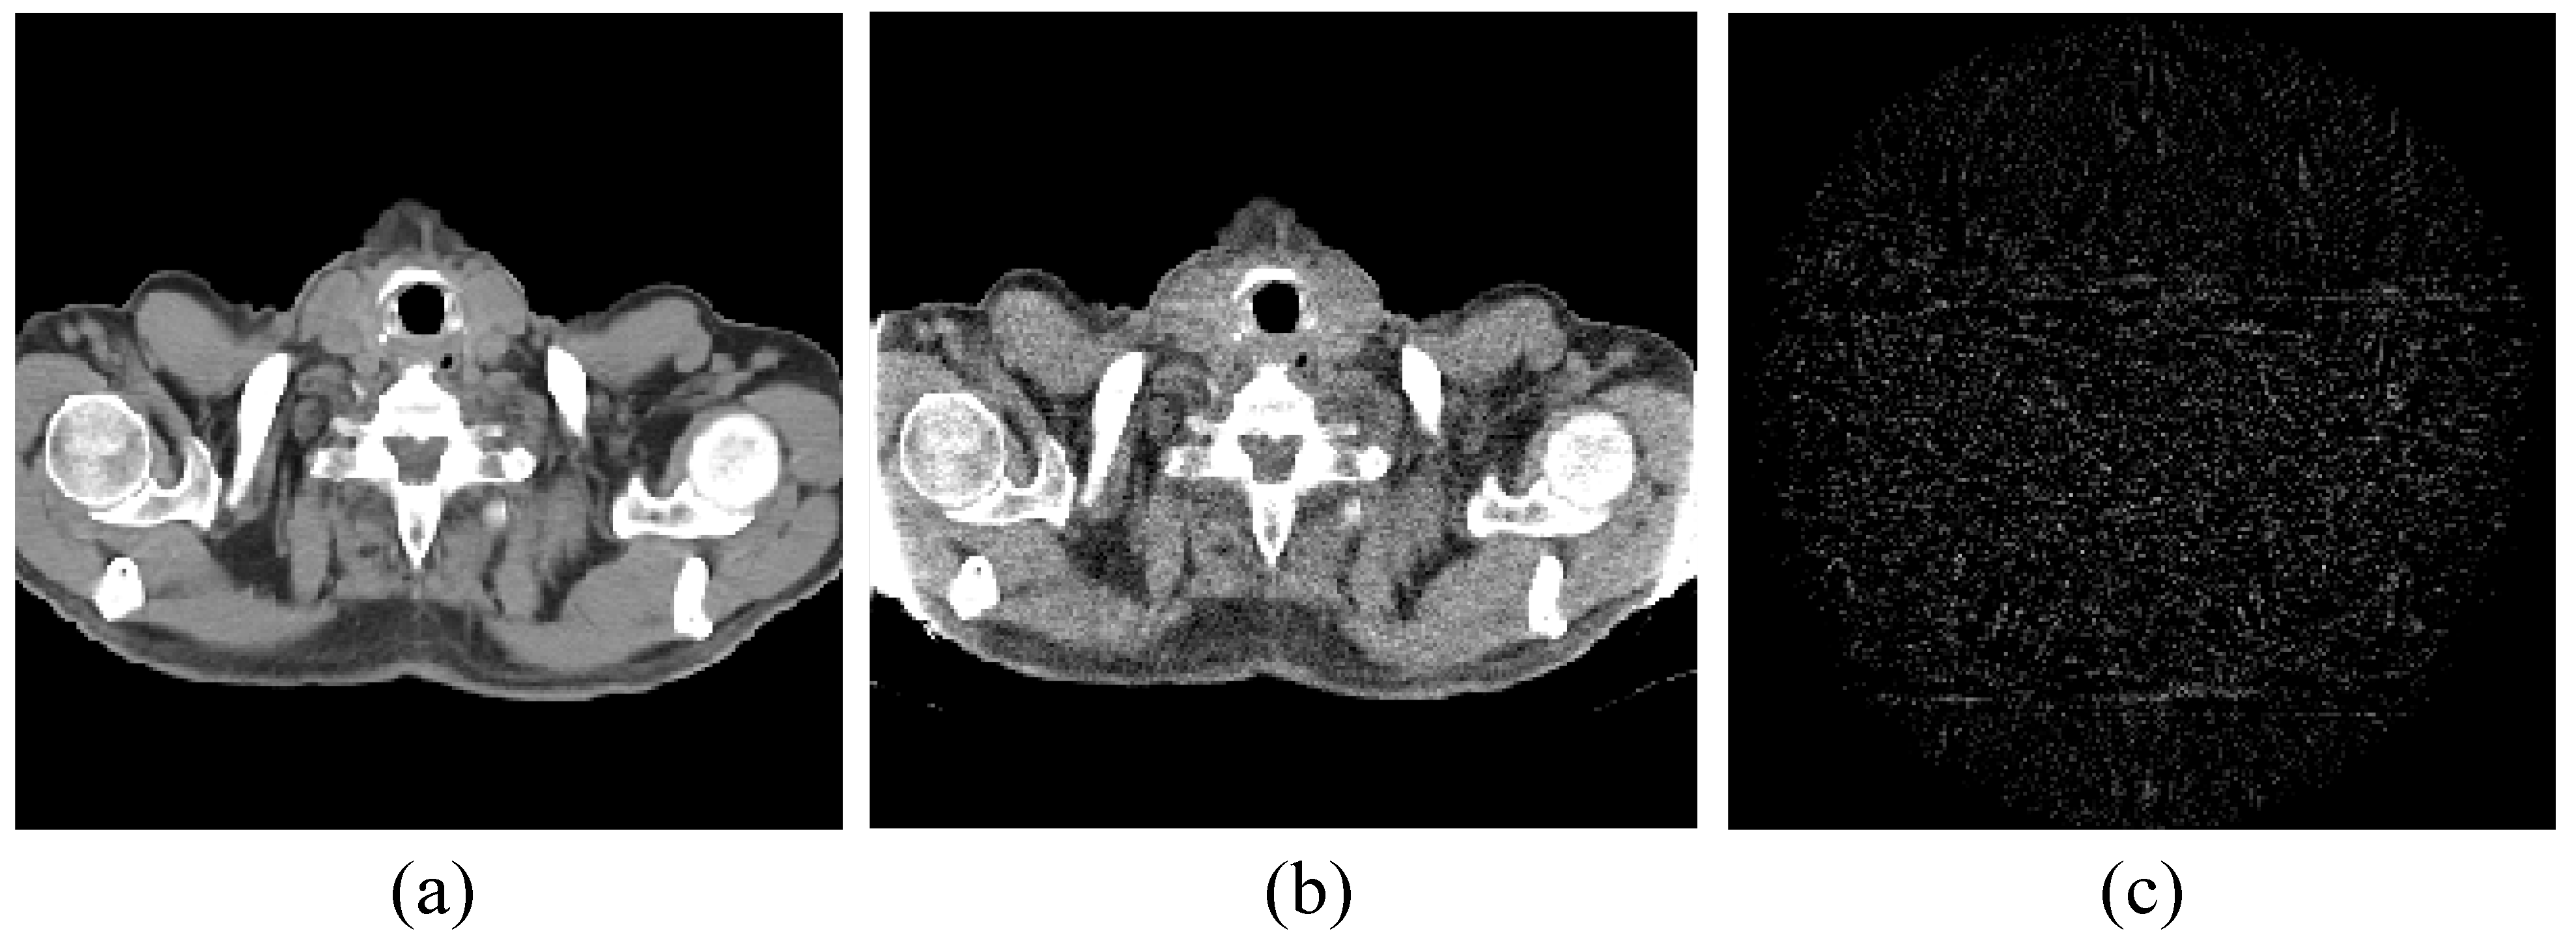

4.1. Image Reconstruction Experiment of Pelvic Image

Figure 1. Pelvic image for the experiments: (a) the target image; (b) the prior image; and (c) the difference image between the prior image and the target image.